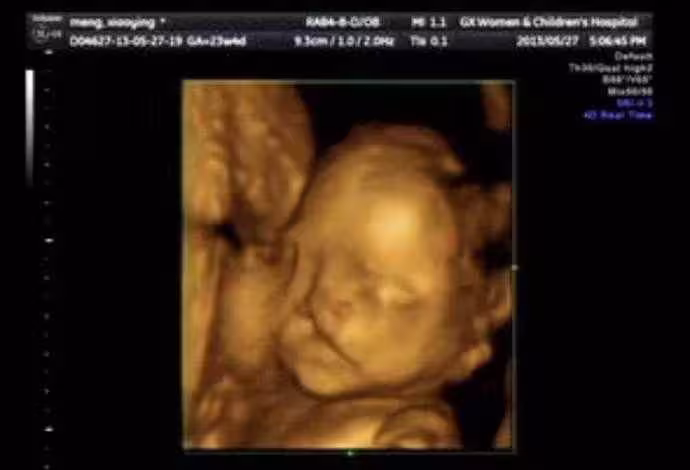

懷孕6個月!23歲孕媽照超音波「寶寶一直在笑」 醫生皺眉勸:「孩子不能留」‼️

相信每個媽媽懷孕時,最期待的就是產檢照超音波了吧!這個偉大的科技發明,除了可以讓准父母提前知道寶寶的性別,同時也能趁機跟他打招呼,看著孩子在肚子裡翻身,有些媽媽甚至會感動得哭出來。